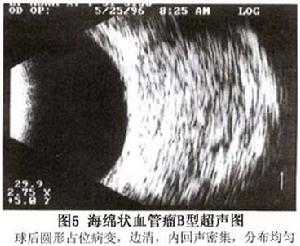

(2)B型超聲探查:海綿狀血管瘤具有獨特的聲像圖,病變呈圓形或橢圓形,有腫瘤暈,邊界清楚,圓滑。內回聲多而強,且分布均勻,中等度聲衰減。以探頭壓迫眼球,可見腫瘤軸徑縮短即壓迫變形腫瘤的內回聲多且分布均勻,是特異性超聲征